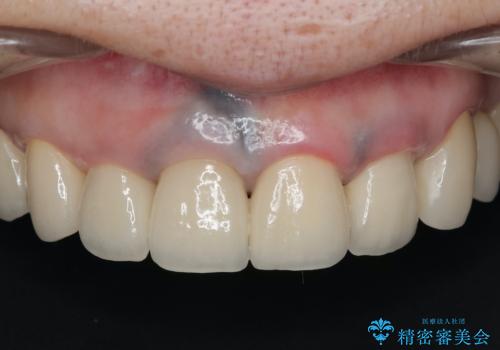

最新の症例

Latest cases